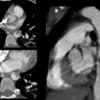

MAI x 2

Unusual location

Date: 08/14/2012

Views: 3183